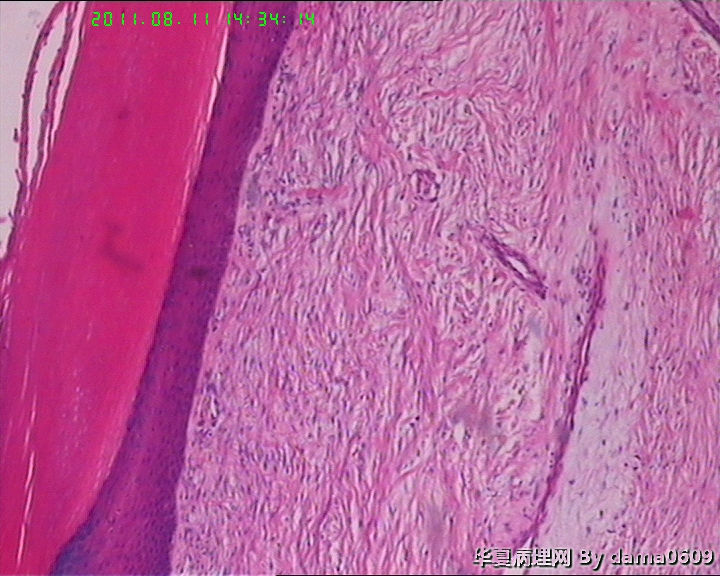

男,14岁,右足第五趾肿物。皮下椭圆形肿物一个,v:2.0x1.7x1.6cm,切面实,灰白,质均,中等硬。

拟诊断:包涵体性纤维瘤病。请老师们指教可否。

(右足第五趾)包涵体性纤维瘤病。

婴幼儿指(趾)纤维瘤病   最特征性的改变是在增生的梭形细胞胞浆内出现包涵体。术后易复发,不转移。